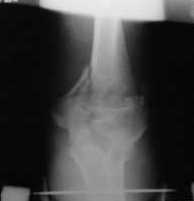

Уважаемые коллеги! Нужен Ваш совет, Подскажите пожалуйста, как можно в дальнейшем этому больному помочь. В марте первая операция, пришлось оперировать на 16 сутки в виду инфицированных садин и анемии. Заживление первичным натяжением,раняя разработка после операции, а через 2 нед болевой синдром,и постепенно движения в локтевом суставе ограничились до полного анкилоза. Повторно через 4 месяца вторая операция" артролиз,удаление оссификатов, удаление фиксаторов, реостеосинтез этой же реконструкционной пластиной и винтом" интраоперационно после удаления оссификатов и фиксаторов обнаружил, что перелом не сросшиеся, поэтому пришлось синтезировать заново. Зажило рана первично, объем движений в локтевом суставе сгибание 70, разгибание160, ротационные движения востановились полностью,вроде бы успокоились. Опять постепенно в течении 8 нед после повторной операции постепенно движения ограничились до 80 - 110, на снимке оссификат. Снимки во вложении, буду рад Вашим советам. Спасибо!С уважением Шухрат.